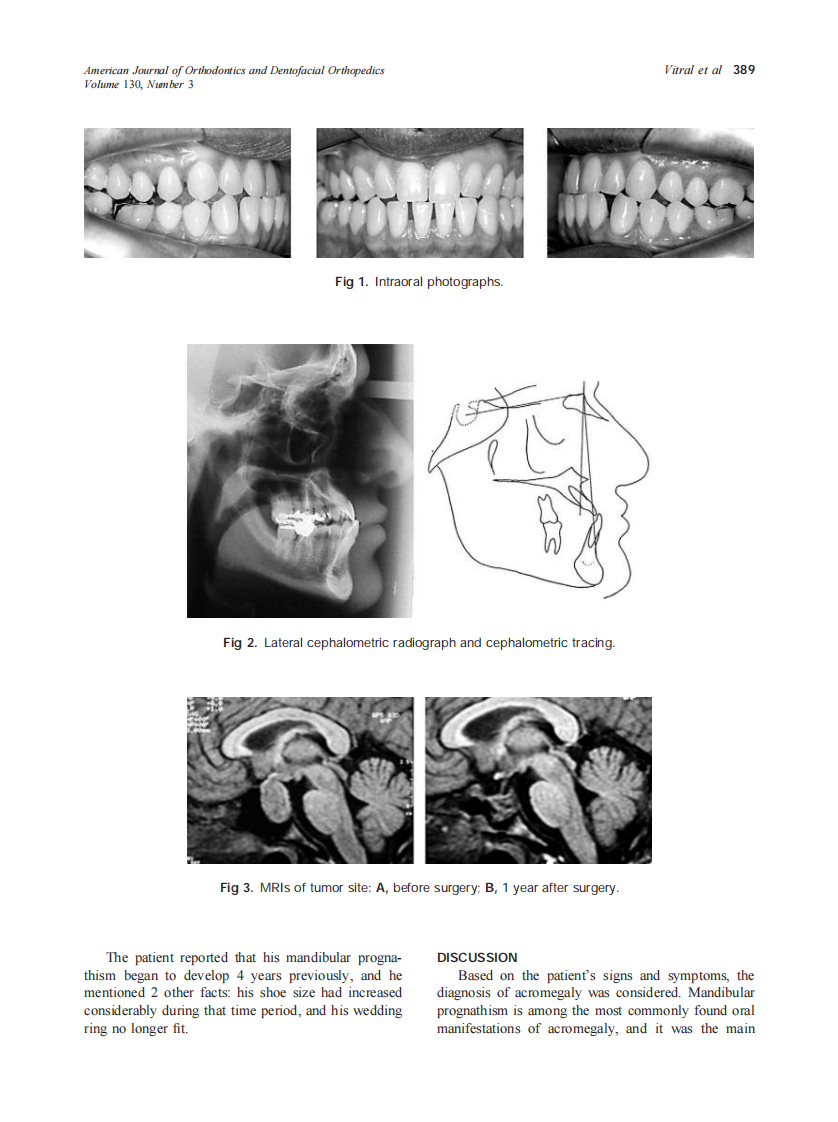

2006_130_3_388_390_Vitral.pdf